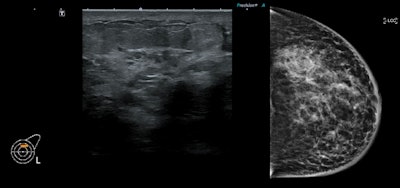

An expected predominant use of ultrasound was observed, with a total of 3,011 ultrasound exams carried out (98.7% of all scans) over the four-year period.

The average age at diagnosis over the four-year period was 31.8, and 18 of the 36 patients diagnosed with cancer from 2018-2021 were referred with a "likely benign" clinical examination indicated by an E3 score. The average size of tumor mass seen on ultrasound per year was 33.4 mm in 2018, 46 mm in 2019, 40.2 mm in 2020, and 49.86 mm in 2021.